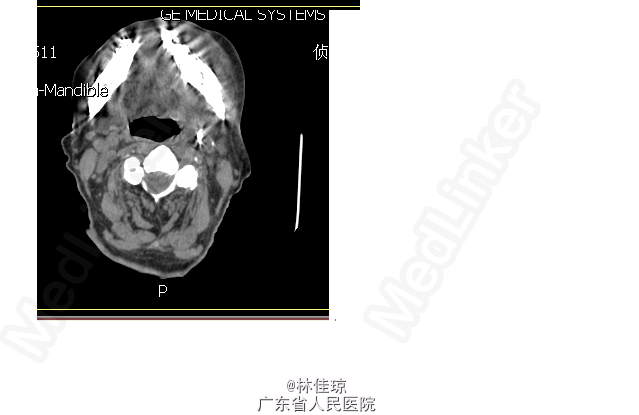

体查:头部不自主摆动,颈软,口腔异味,口腔未见明显出血点,可见少许血块。左下颌骨处可扪及4cm*1cm大小肿物,质硬,不可移动,局部皮温稍高,无触痛,表面未见分泌物。心肺腹查体未见明显异常。 行口腔科会诊,口腔科医师考虑左下后牙残根,牙龈红肿,探之易出血,建议予依信漱口。 大便常规:OB阴性, 血常规、PCT正常。 肿瘤指标正常; 凝血指标正常。 肾ECT:双肾总GFR 25.2ml/miin。 下颌骨CT未见明显异常,建议行下颌骨增强CT以排除局部感染或肿瘤; 下颌骨彩超:左下颌骨皮下软组织内实质性肿块,建议进一步检查。 胸片正侧位放射常规照片:慢支炎肺气肿。主动脉硬化。

1.下颌骨肿物查因:下颌骨炎症?下颌骨肿瘤?2.脑梗塞 该患者头部不自主摆动,无法配合行下颌骨X片,双肾总GFR 25.2ml/miin ,暂不考虑行CT增强检查。考虑炎症可能性大,暂予头孢+甲硝唑抗感染治疗及依信对症漱口治疗。

目前患者考虑下颌骨炎症,暂予头孢+甲硝唑抗感染治疗,但患者血常规、PCT正常,局部肿物质地硬,与下颌骨粘连,且不可移动,查肿瘤指标正常及CT未见肿物,该局部肿物是否有其他可能?